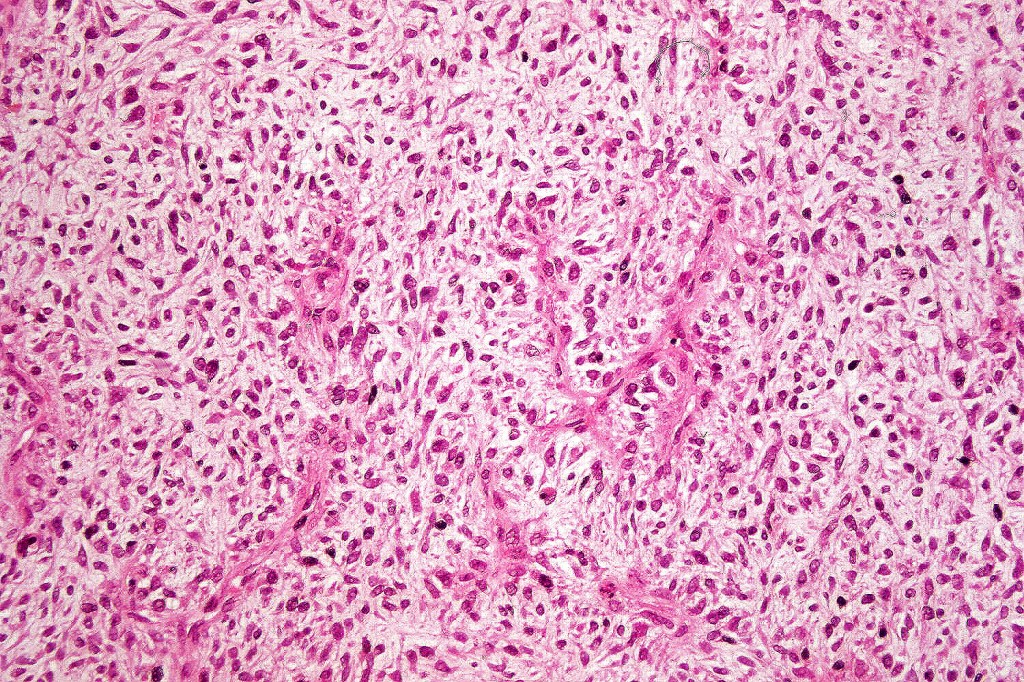

•Biphasic tumor

•Possible epithelial to mesenchymal transition

•Admixture of squamous carcinoma & pleomorphic spindled cell, osteoid, chondroid, MFH-like +/- osteoclast-like giant cells & rarely, smooth muscle, skeletal muscle, myofibroblastic or angiosarcomatous elements